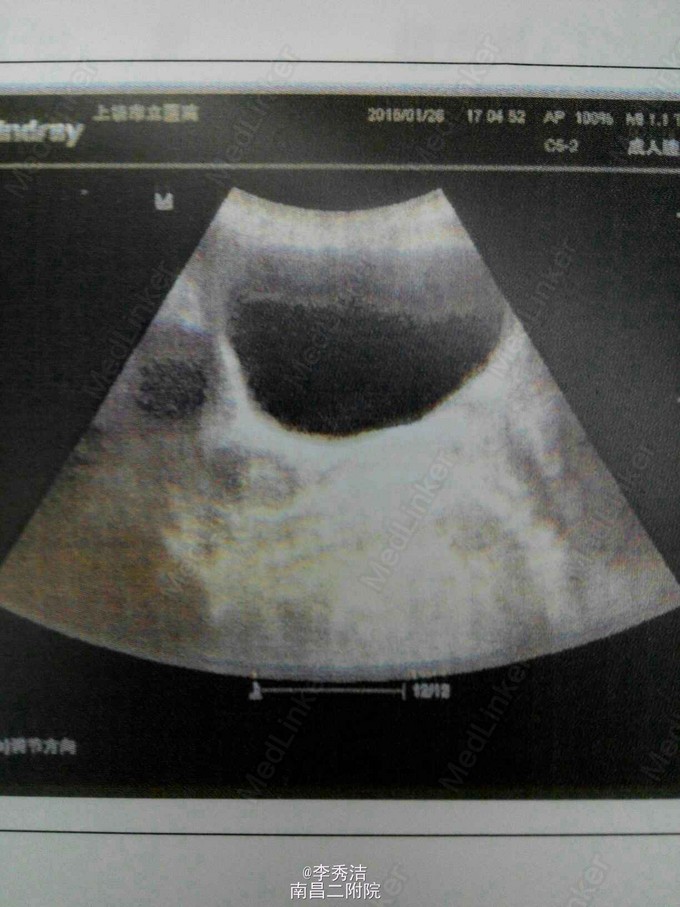

患者女,55岁,一周前体检发现宫颈癌,无任何自觉症状。诊断性刮宫病理结果示:子宫颈中分化浸润性磷状细胞癌。给予全子宫+双附件切除加盆腔淋巴结清扫,后期予顺铂+紫杉醇化疗。